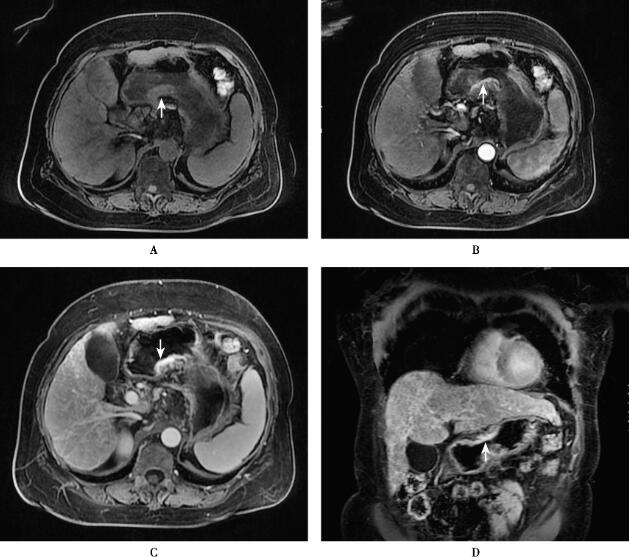

图1 胃癌(T3N1)

图2 肝硬化结节癌变

肝硬化结节癌变的T1WI多呈低信号,T2WI多呈高信号,增强扫描典型表现为“快进快出”。

胃癌T3N1,肝右叶肝硬化结节癌变。

就此例患者而言,MRI平扫显示其肝硬化背景及肝右叶占位性病变,增强扫描“快进快出”的表现将其与肝转移瘤鉴别。此例患者肝转移瘤及肝癌的鉴别,对治疗方案的选择有非常重要的意义。